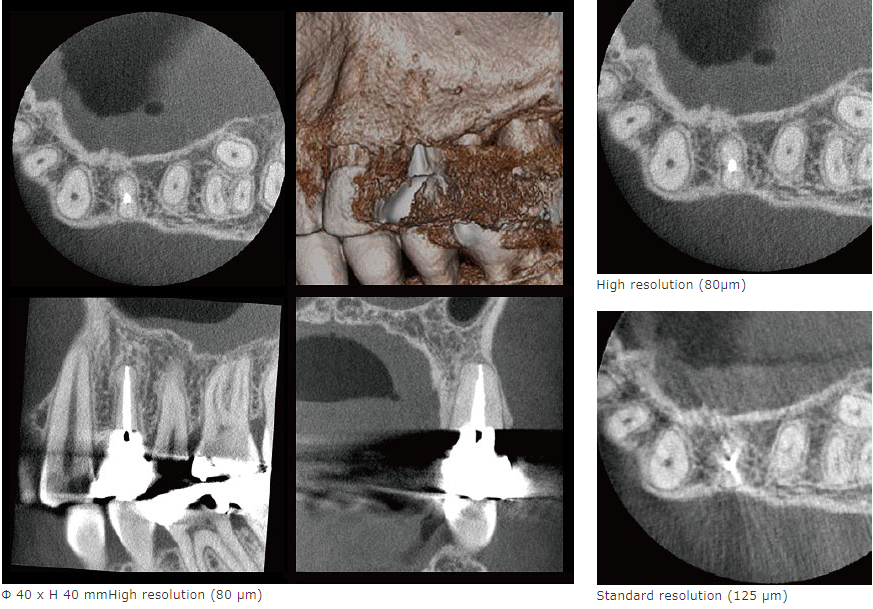

FOV Φ40xH40の撮影では、ボクセルサイズ80µm、2.5LP/mm以上の高解像度CT撮影を実現しました。上の例では、125µm画像に比べ80µm画像の方が、アーチファクトが少なく、鮮明に描出しています。

*空間分解能は、空間的にどの程度小さいものが見分けられるかを示します。一般的に空間周波数(ラインペア: LP/mm)で評価 されます。これは1mmの空間に含まれる明暗を一組にした縞模様が何組識別できるかを指標とするもので、数値が高いほど解像度が高いことを表します。MTF(Modulation Transfer Function)は、ラインペア解像度の客観的な評価方法のひとつで、何ラインペアがどのくらいのコントラストで識別できるかを客観的に表すものです。一般的に、MTFが10%あれば目視での識別が可能であるといわれています。空間分解能はボクセルサイズだけで決まるものではありません。